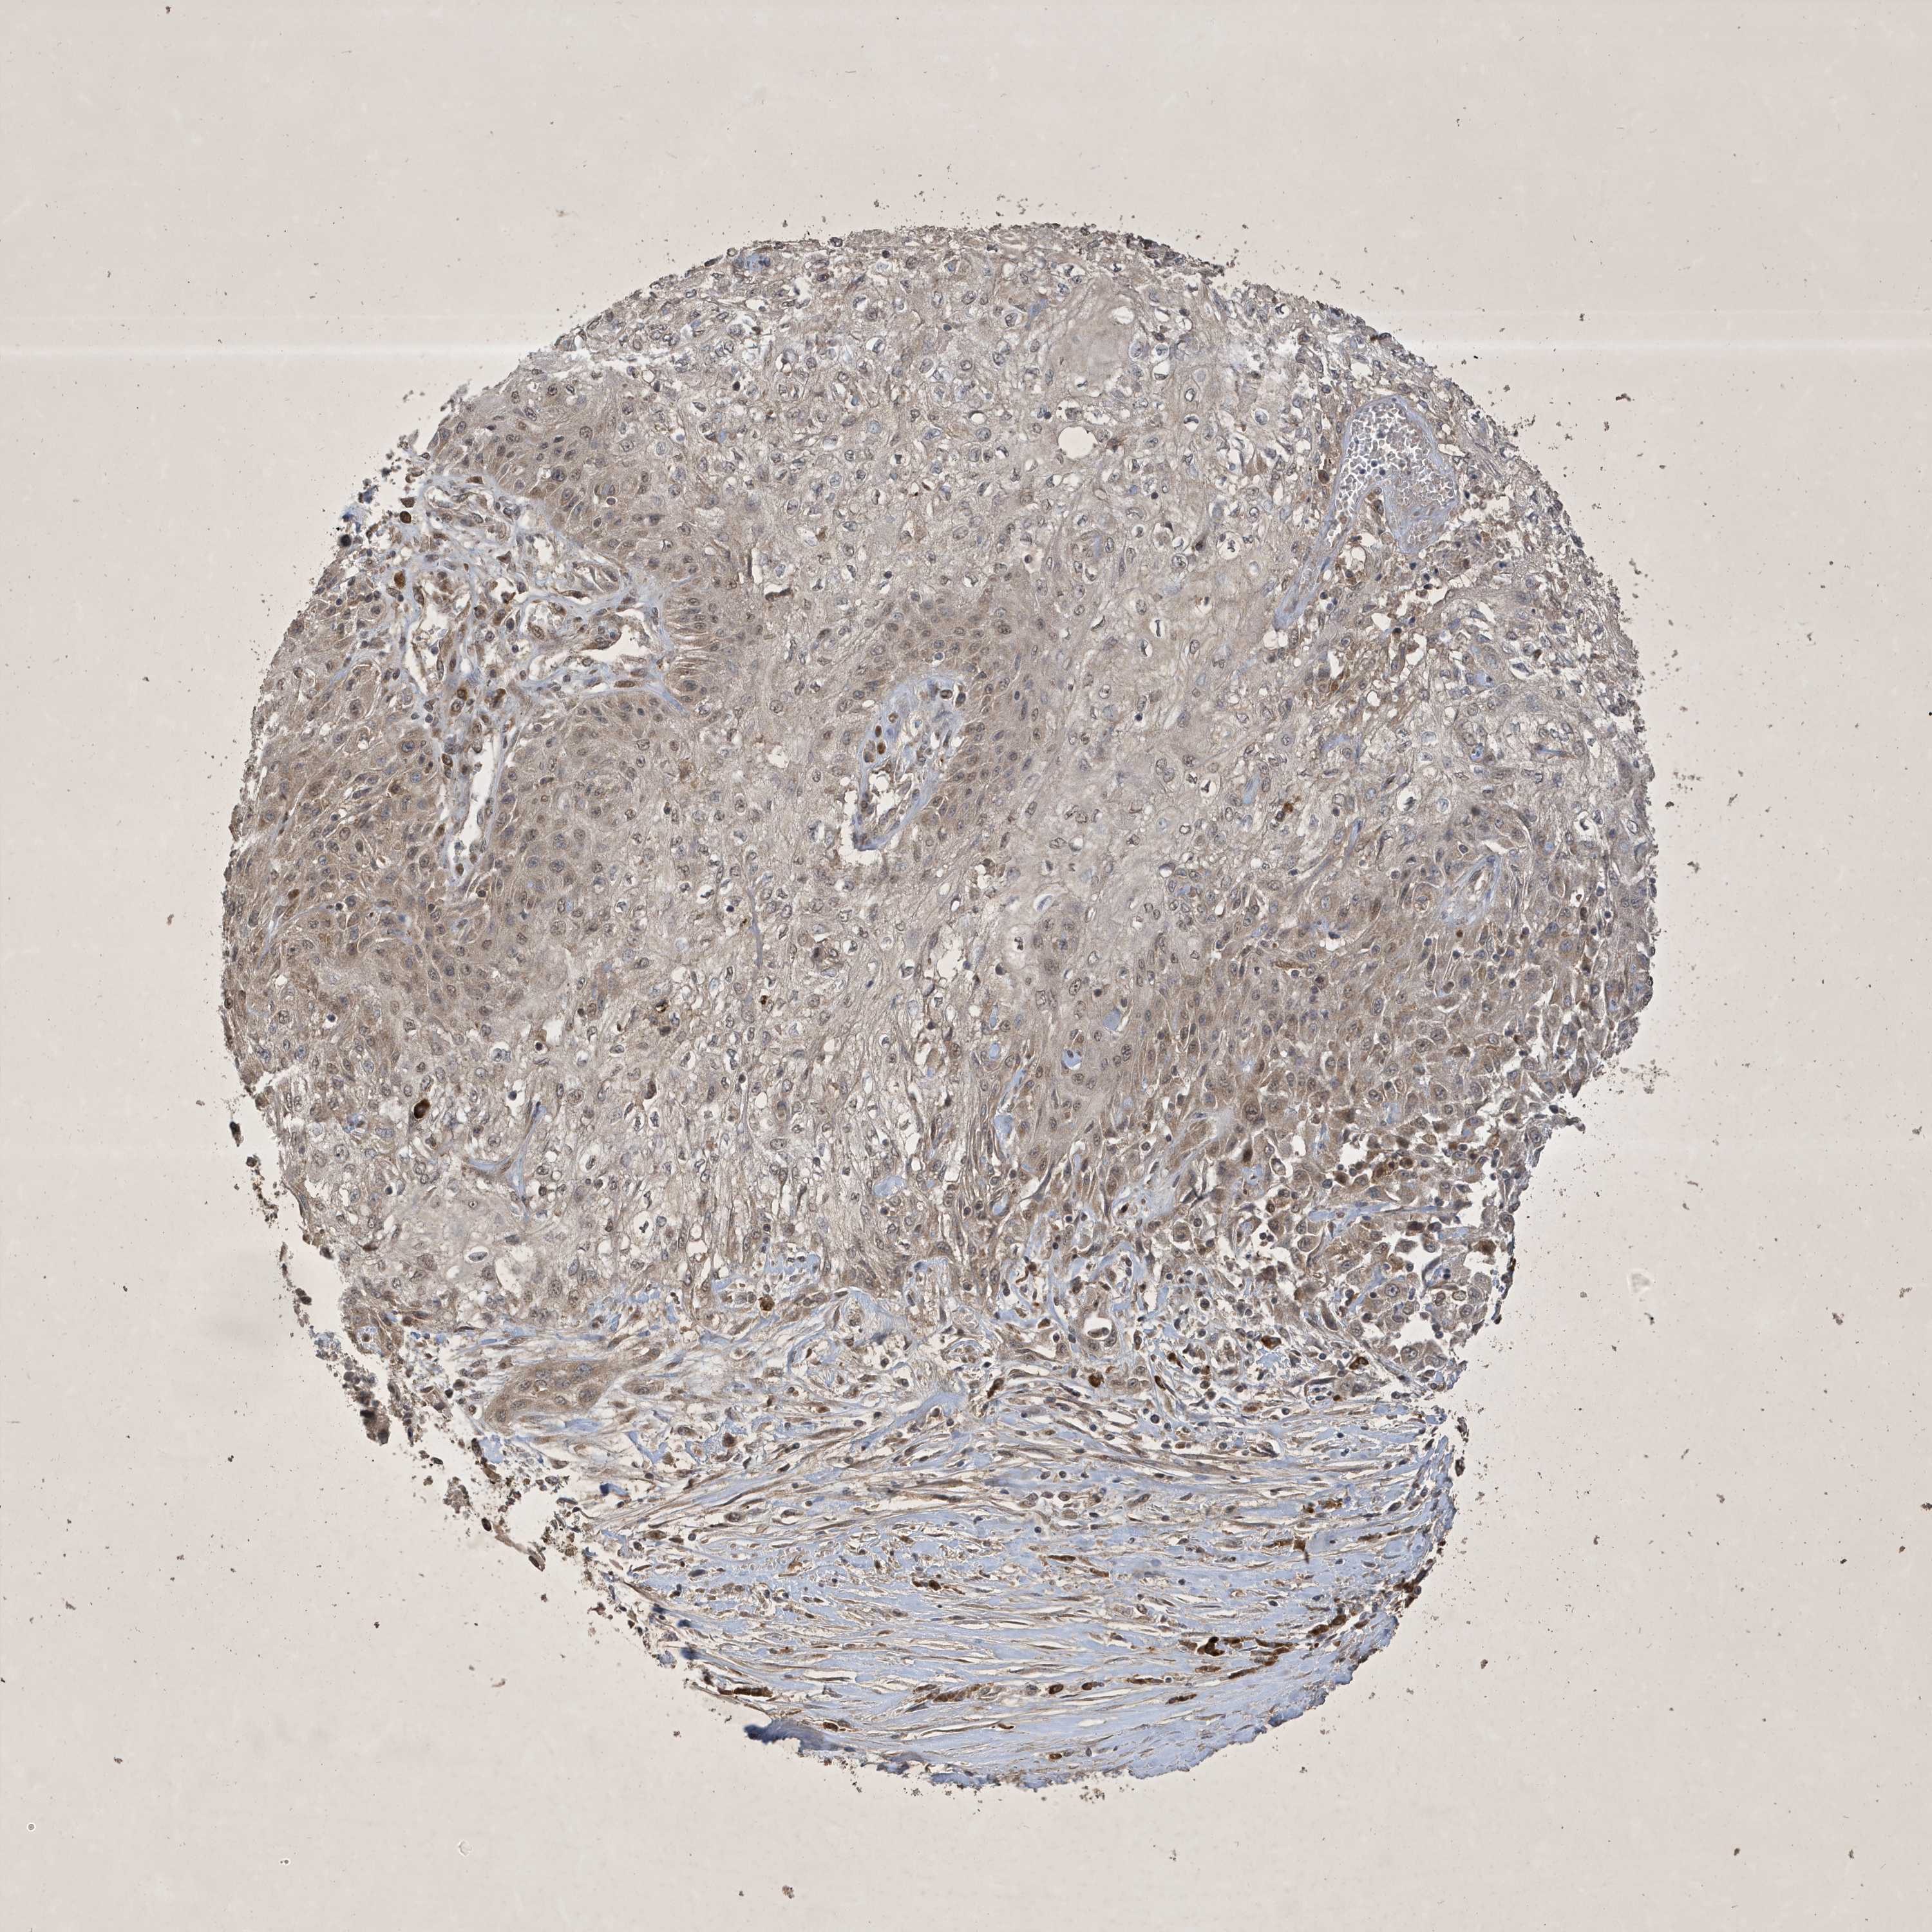

SKIN CANCER - Protein expressioni

A mouse-over function shows sample information and annotation data. Click on an image to view it in a full screen mode. Samples can be filtered based on level of antibody staining by selecting one or several of the following categories: high, medium, low and not detected. The assay and annotation is described here.

Antibody stainingi

Antibody staining in the annotated cell types in the current human tissue is reported as not detected, low, medium, or high, based on conventional immunohistochemistry profiling in selected tissues. This score is based on the combination of the staining intensity and fraction of stained cells.

Each image is clickable and will lead to virtual microscopy that enables deeper exploration of all samples and also displays staining intensity scores, fraction scores and subcellular localization as well as patient and tissue information for each sample.

Antibody HPA035303

Staining

High

Medium

Low

Not detected

Intensity

Strong

Moderate

Weak

Negative

Quantity

>75%

75%-25%

<25%

None

Location

Nuclear

Cytoplasmic/membranous

Cytoplasmic/membranous,nuclear

Squamous cell carcinoma, NOS

Squamous cell carcinoma, metastatic, NOS